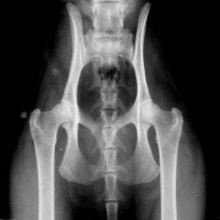

Helse er av høyeste prioritet, og derfor tester jeg utover det som er pålagt for oppdrettere i NRR. Jeg har fokus på primært HD og noe HCM, og røntger mine avlsdyr før eventuell paring.